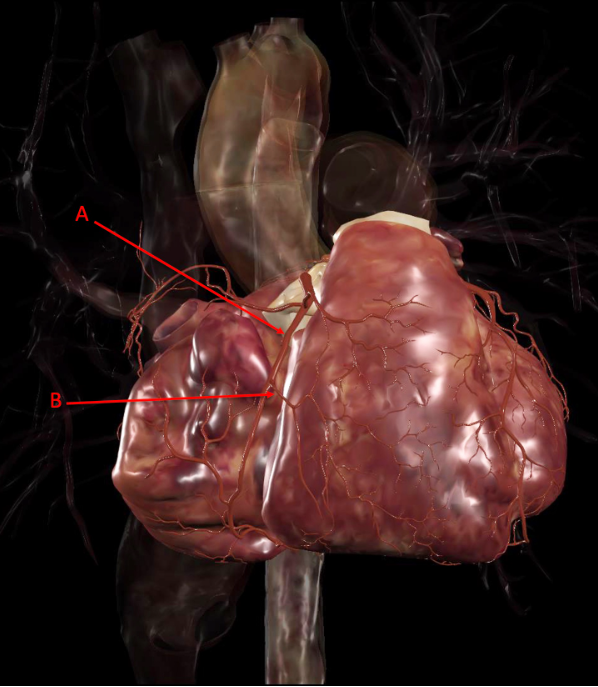

Q

Identify the following structure(s)

A

A. anterior interventricular artery

B. left circumflex artery

C. marginal or posterior interventricular artery